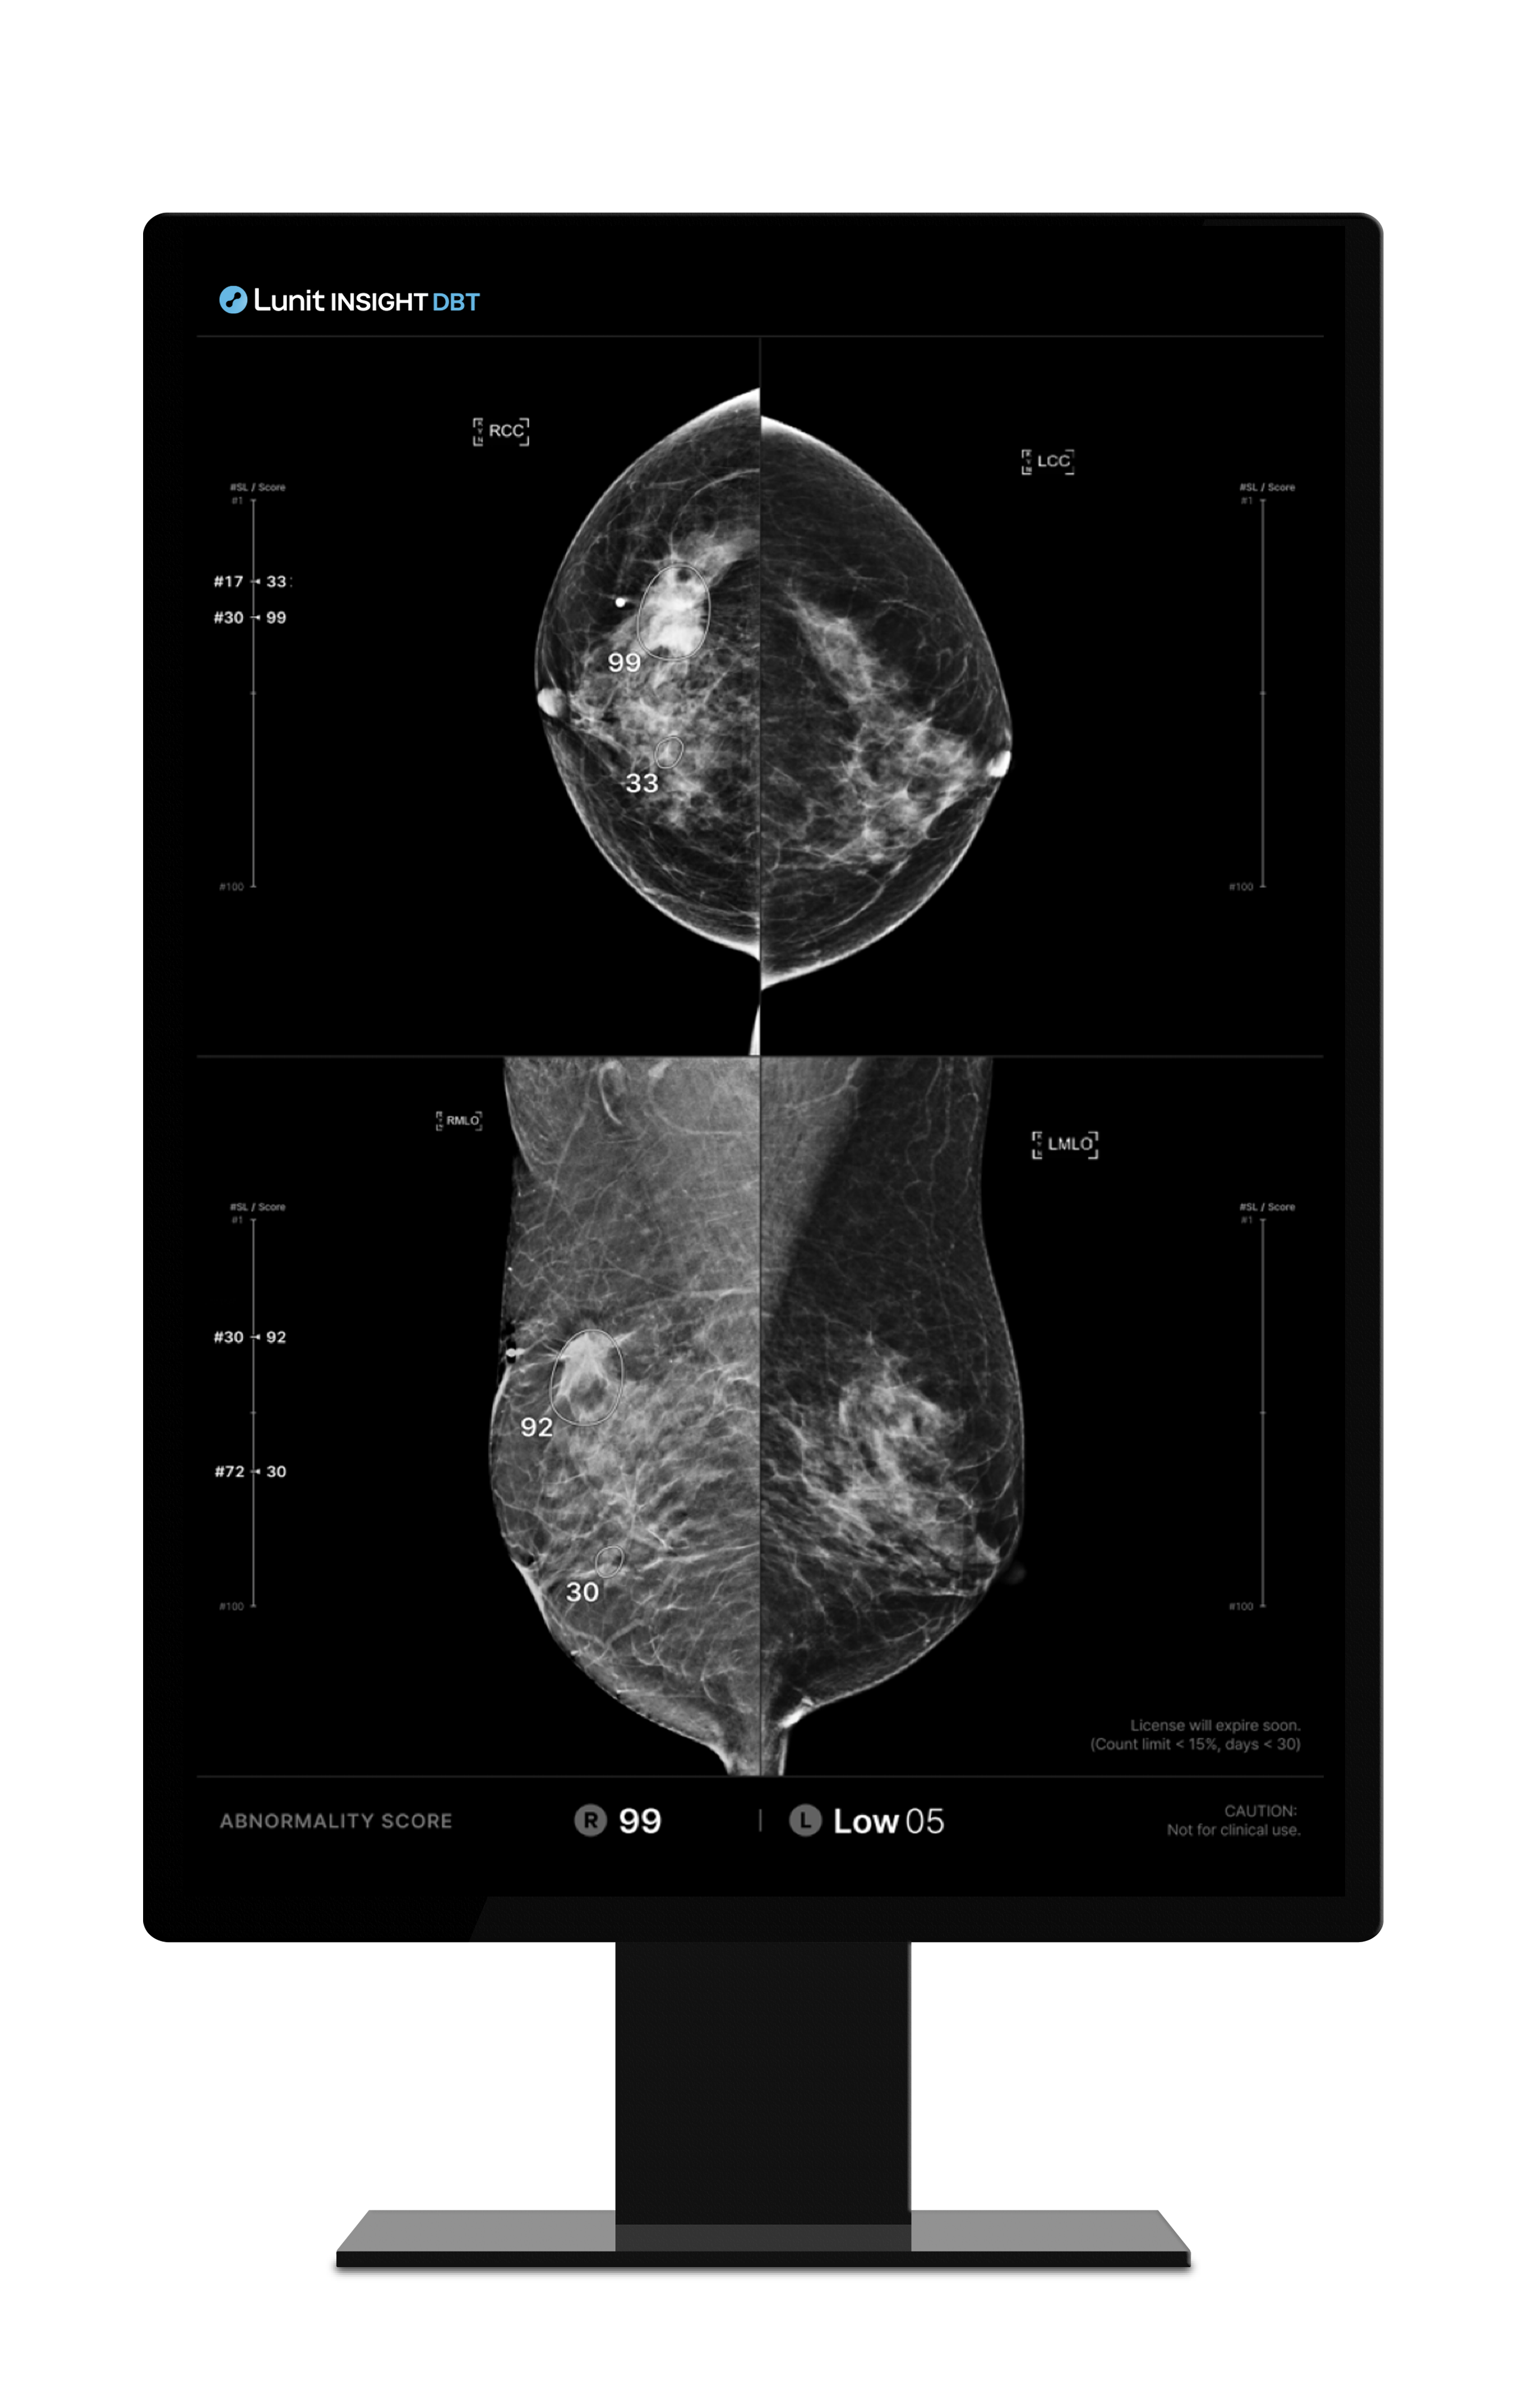

루닛 인사이트 DBT는 3D Tomosynthesis 영상을 분석하여 유방암 의심 부위를 검출합니다.

유방암 의심 부위의 존재 가능성을 0-100의 숫자로 나타냅니다. 숫자가 높을수록 악성 병변의 존재 가능성이 높습니다.

결과영상 화면 종류:

결과영상 화면에서 병변이 검출된 슬라이스의 번호와 점수를 확인(SC)할 수 있고, 클릭 시 해당 슬라이스로 바로 이동(CAD SR) 할 수 있습니다.